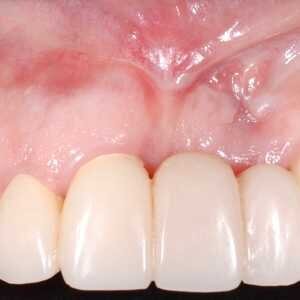

Dans cet article, nous présentons un cas clinique qui montre comment une mauvaise mise en place d'un implant peut rendre impossible la réhabilitation prothétique, ce qui nécessite une nouvelle planification chirurgicale et de réhabilitation pour obtenir l'esthétique souhaitée. Le patient se présente à notre observation avec une réhabilitation prothétique incongrue, avec bride en résine, support dentaire et implantaire, avec la présence d'un implant en position 2.1 vestibulaire et avec l'émergence dans le fornix, dans la mucosa alvéolaire. L'évaluation de la tomodensitométrie montre la position incorrecte de l'implant et la perte constante dans le sens transversal de la structure osseuse (Figs. 1, 2). Par conséquent, le plan de traitement suivant a été choisi : retrait de l'implant et préparation prothétique de l'élément 2.3, fabrication d'un premier support dentaire temporaire pour guider la cicatrisation des tissus (Figs. 3-7). Après 4 mois, une greffe d'épithélium conjonctif libre est réalisée avec ablation du palais pour compenser l'espace transversal des tissus mous, puis le provisoire est remodelé afin de faciliter la cicatrisation des tissus (Figures 8-11). Après 9 mois de maturation des tissus, la finalisation prothétique fixe avec support dentaire est réalisée (Figs. 12-14).

Quelle qu'en soit la cause, lorsqu'un implant n'est pas bien placé, la réhabilitation prothétique peut ne pas être adéquate sur les plans mécanique, fonctionnel et esthétique. Dans le cas présenté ici, le retrait de l'implant et une nouvelle planification chirurgicale et prothétique étaient nécessaires. Malgré les limites esthétiques de la réhabilitation prothétique initiale, considérant qu'aucune greffe osseuse n'a été réalisée sans réinsertion de l'implant, mais avec une bonne gestion des tissus mous, un résultat esthétique valide et prévisible a été obtenu avec le temps.